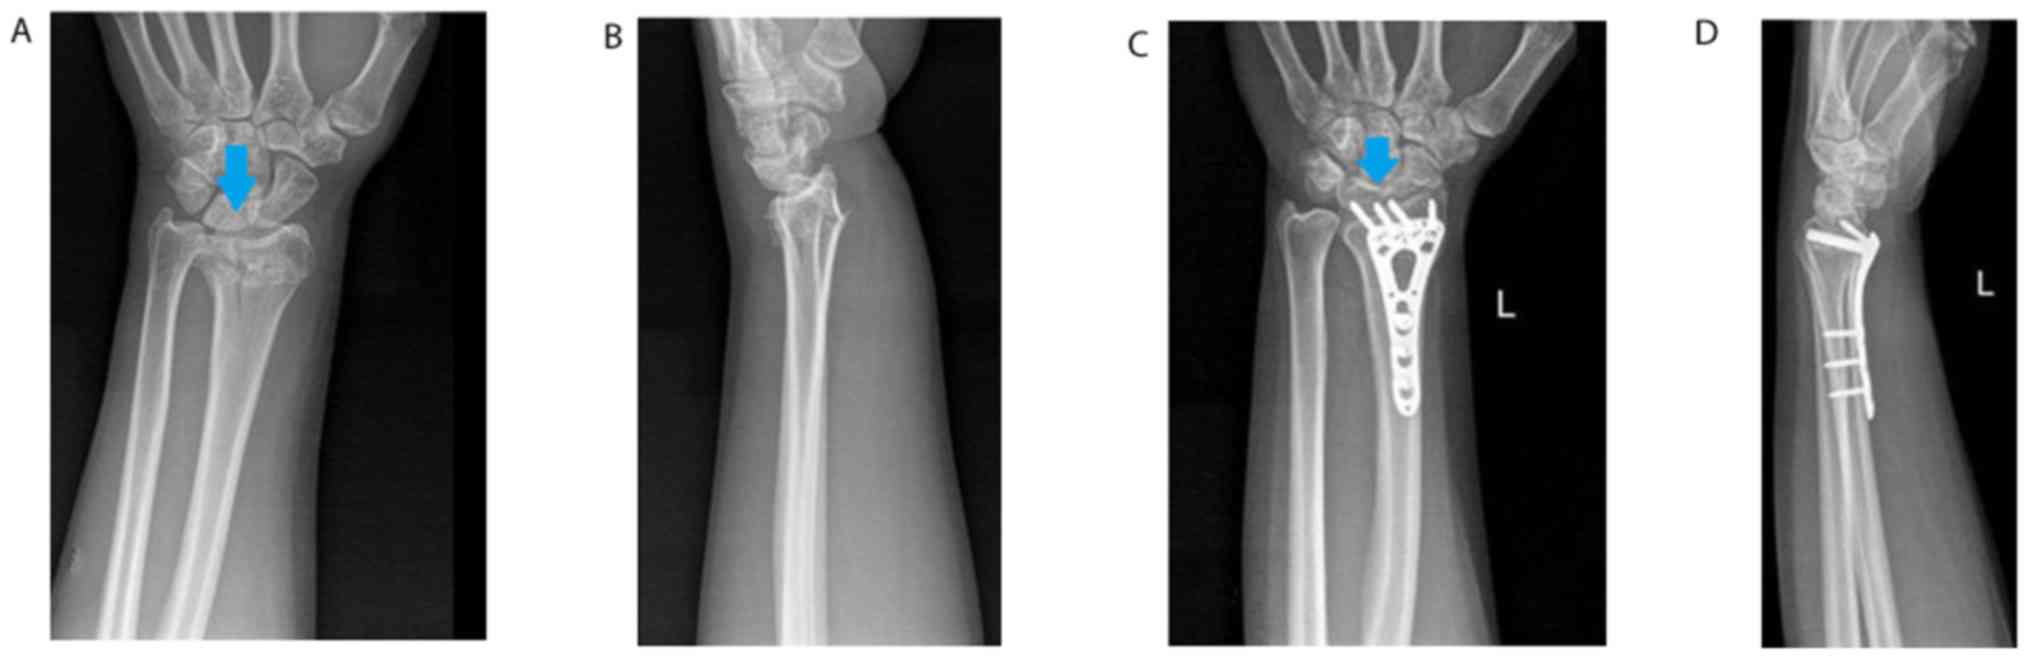

Treatment outcomes vs. fracture type

Figure 4.

Successful surgical treatment of a type III fracture. (A) Anteroposterior and (B) lateral radiographs of the fracture prior to treatment. (C) Anteroposterior and (D) lateral radiographs of the fracture after the treatment. The arrow indicates the fracture site.